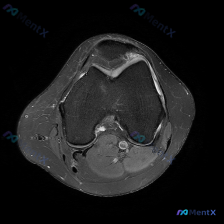

看到一份膝关节轴位MRI的读片资料,软骨异常是核心发现,整理了影像特征和完整分析思路,和大家分享讨论。 一、影像基本信息 这是膝关节髌股关节层面的脂肪抑制序列MRI(PD-FS或T2-FS),图像特征: 1. 髌骨、股骨皮质低信号,骨髓脂肪信号正常 2. 核心异常:髌骨后方关节软骨信号不均匀,局部高...

刚看到这份膝关节轴位MRI的分析资料,整理一下思路,这个病例其实挺容易踩坑的,分享给大家一起讨论。 病例影像核心信息 本次提供的是膝关节轴位MRI(T2WI/质子密度脂肪抑制序列),核心发现如下: 1. 髌股关节:髌骨软骨面全层高信号改变,股骨滑车中央及内侧软骨也可见广泛高信号;髌股关节间隙可见明显...

刚看到一例膝关节MRI读片的病例,整理了完整的影像发现和分析思路分享给大家,这个病例其实挺容易踩坑的。 病例影像资料 这是膝关节MRI T2序列轴位图像,读片结果整理如下: 1. 髌股关节: 髌骨后方关节软骨不连续,信号增高、形态毛糙,可见片状高信号,提示软骨损伤磨损;股骨滑车关节面软骨同样信号增高...